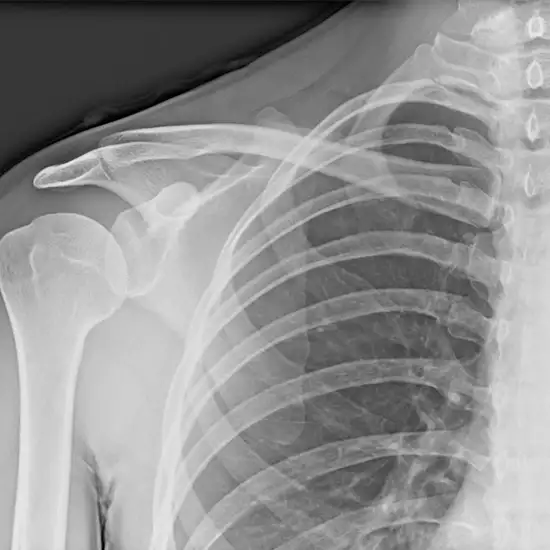

An X-ray of the scapula (shoulder blade) visualizes the shoulder blade and the surrounding soft tissues (skin and muscles). The scapula is a bone with a triangular shape that connects the collarbone to the upper arm bone and chest wall.

• To diagnose any scapula (shoulder blade) fractures and monitor the healing of the fractured bone after it has been set.

• To diagnose any suspected infection, osteoporosis, deformities, or abnormal bone growth.

• To diagnose winged scapula (a condition in which the shoulder blade protrudes from the back).